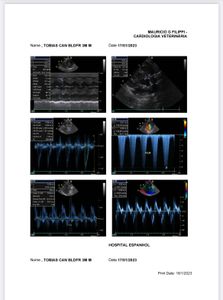

Tobias é um Bulldog francês de apenas 5 meses de vida. Nasceu com uma obstrução em uma válvula do coração, doença chamada de Estenose Pulmonar. Seu coraçãozinho não consegue bombear o sangue de forma adequada pro órgãos, devido a válvula ser muito apertada pra permitir o fluxo adequeado de sangue. Isso faz com que o sangue se acumule em um lado do coração, deixando-o com insuficiência cardíaca, acúmulo de líquidos e dores internas devido o inchaço e pressionamento dos órgãos.

Sem a cirurgia de Correção por Valvoplastia Pulmonar por Balão (inserção de um balão pra abertura da válvula) ele não sobrevirá mais que algumas semanas.